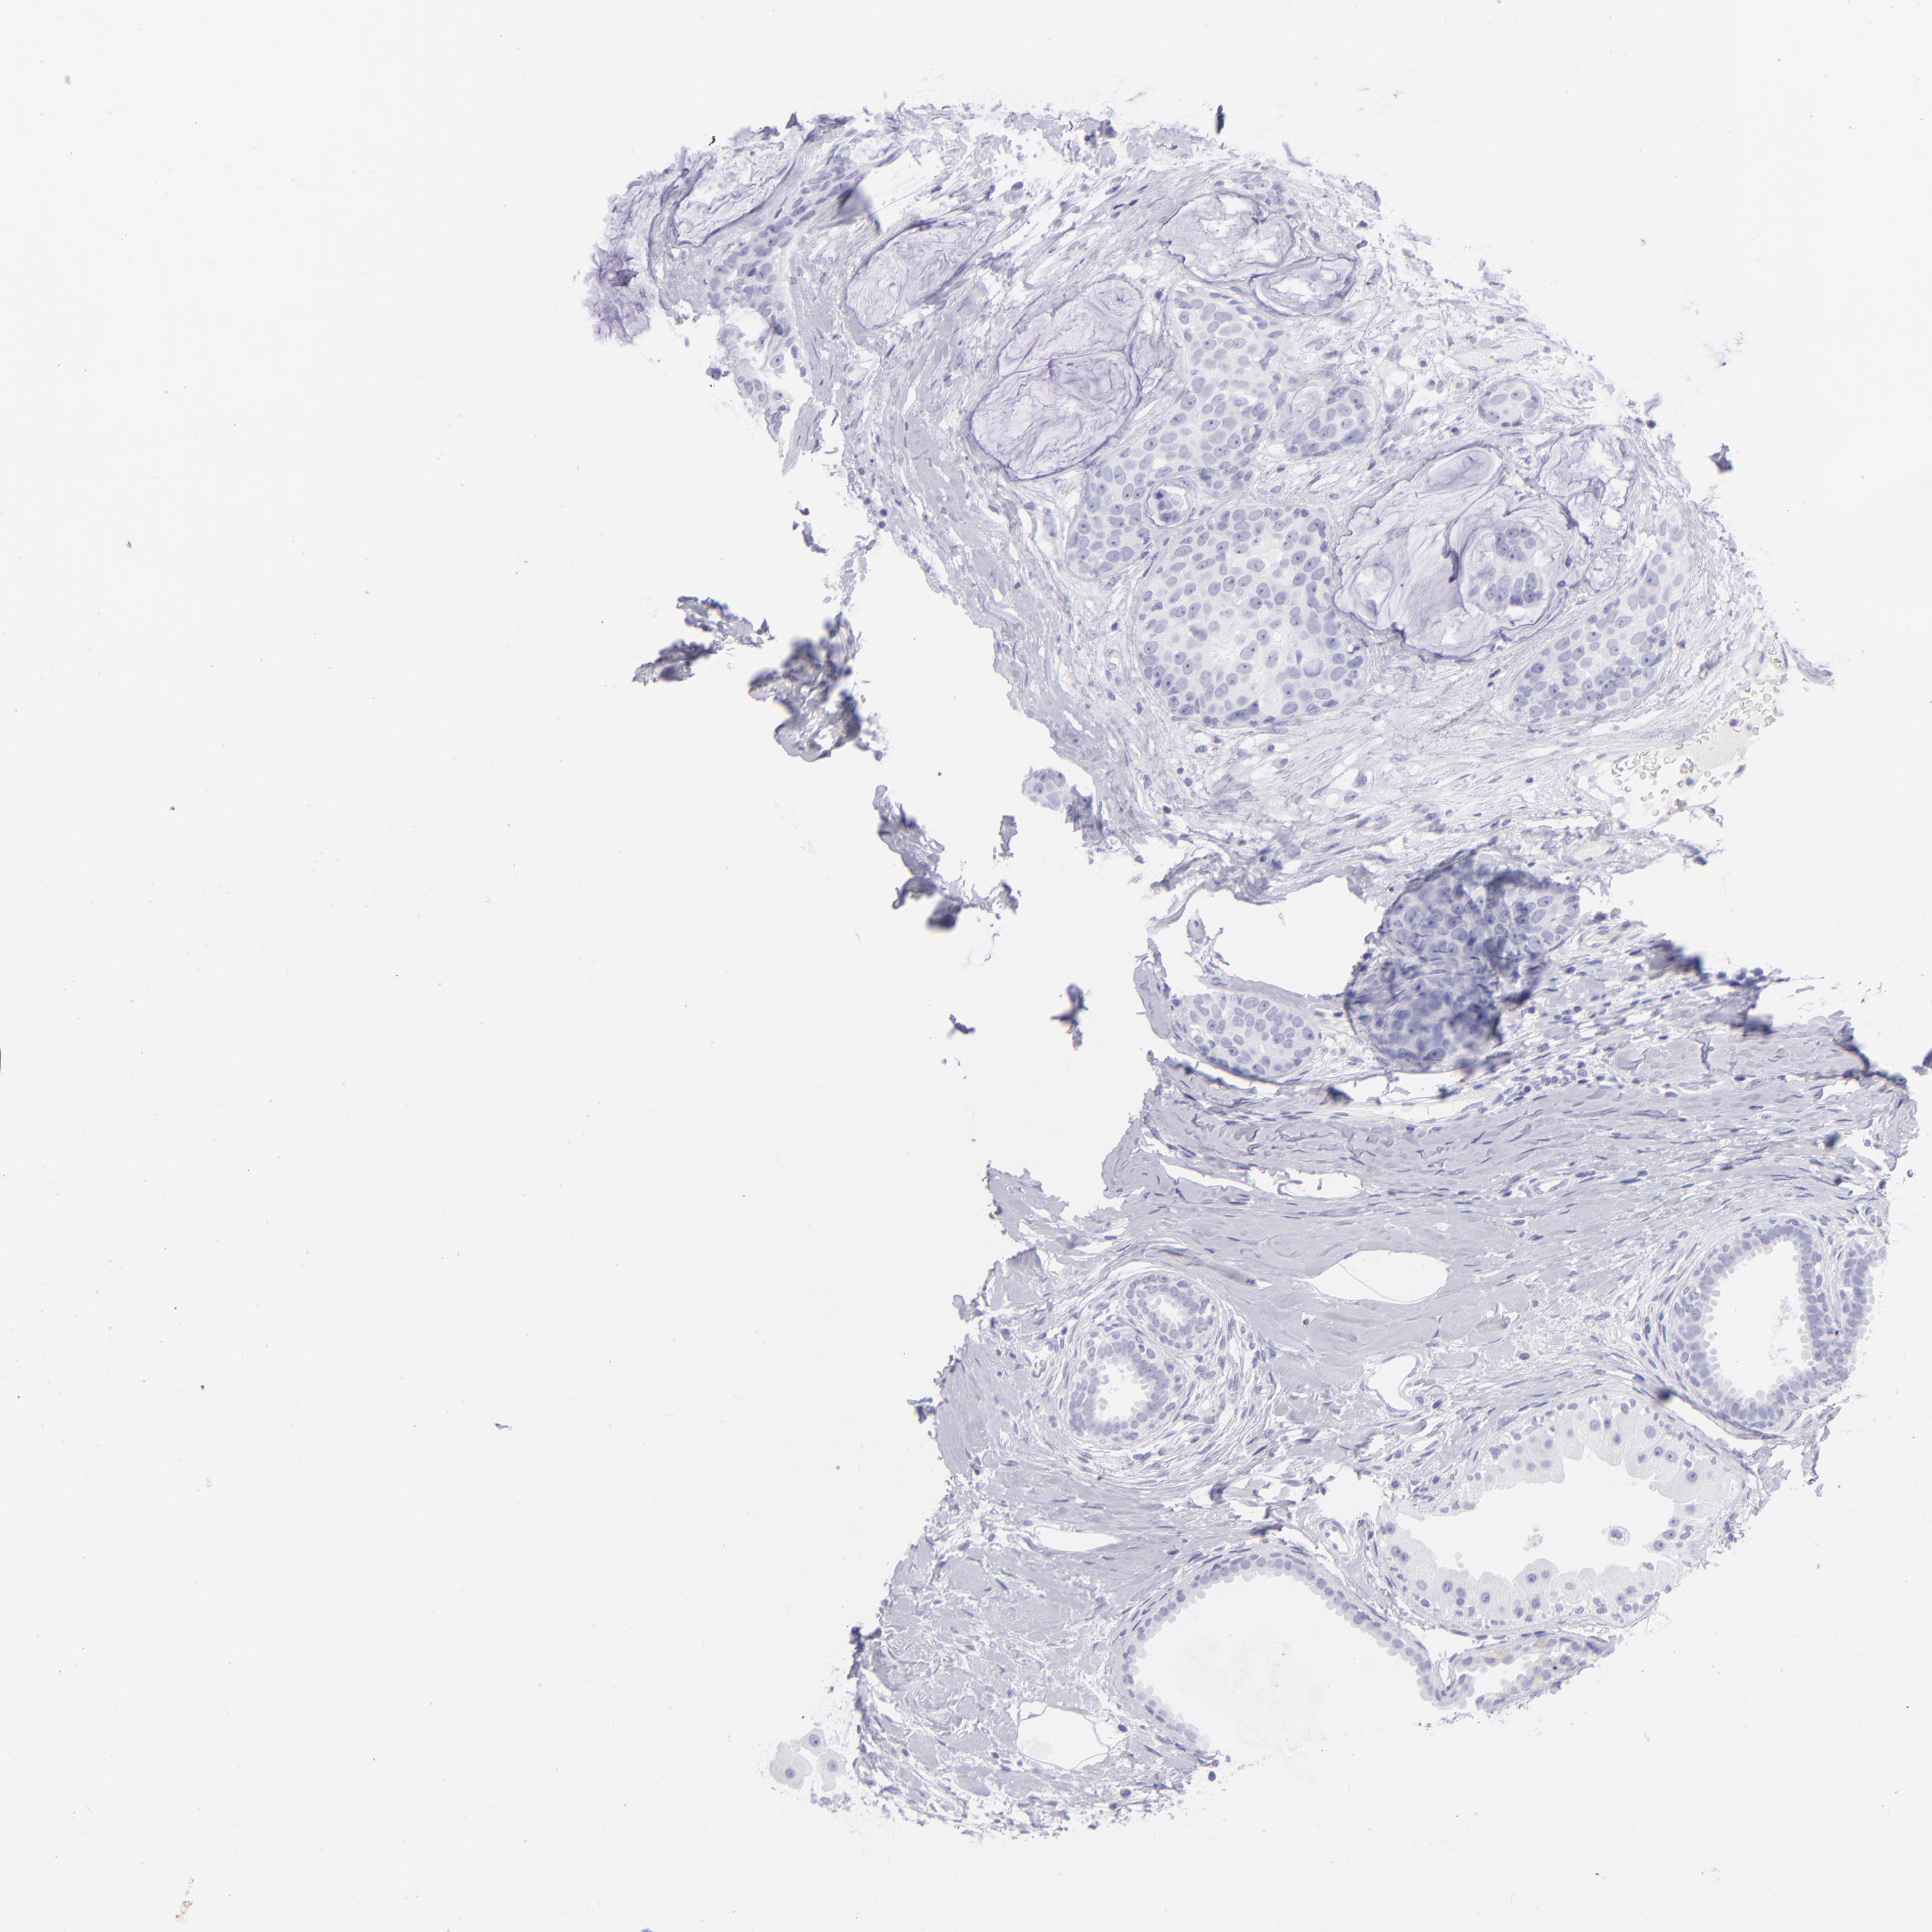

Breast cancer

Human cancer